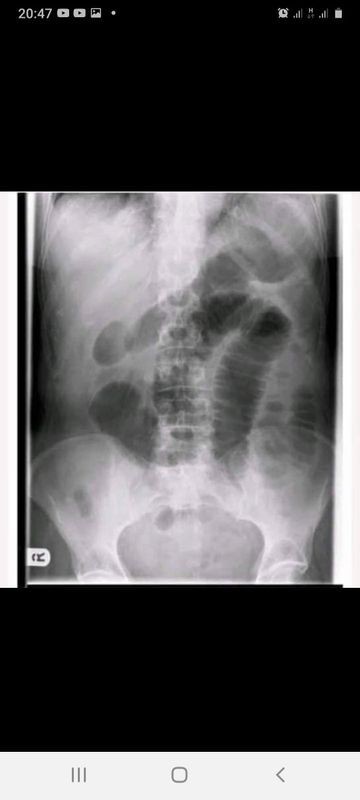

Lagi dan lagi masalah mpasi dini!!! 😡😠😠😠 TERUNTUK MAMAK MAMAK MUDA KEKINIAN. Pagi ini kesel luar biasa.. mau marah tpi ga bisa 😌😌😌 Tepat nya pukul 04.20 wib. Datang seorang ibu dengan membawa bayi usia 29 hari ke UGD.. saat di anamnese oleh dokter, di dapati, Keluhan: sesak nafas sejak tadi subuh jam 04.00 wib (berarti sejak stengah jam sebelum masuk rumah sakit). Dikatakan pasien rewel sejak tadi sore. Selain itu pasien juga mengeluh batuk sejak 3 hari lalu. Tapi batuknya sesekali saja. Mual (+), muntah (-), bayi terasa hangat hangat sejak 1 hari ini. Buang air besar nya normal kok (saat di tanya normalnya gimana: KERAS 😭)sejam sebelum ke Rumah Sakit dia Buang air besar. Nafas udha satu satu.. Spo2 (kadar oksigen diparu cuma 75% yang harusnya 95% keatas loh) kondisi bayi jelek/ buruk/ gagal nafas, sewaktu waktu bisa henti jantung juga.. Pada pemeriksaan fisik semua di dapati normal kecuali ada yang aneh di bagian perut. Perut didapati menggembung dan tegang.. setelah di dengarkan bising usus nya ternyata tidak ada.. Aku langsung tanya, anaknya di kasi makan bubur nggak bu. Dan bener mamak mamak canggih ini kasi bubur kemasan ke bayi nya sejak usia 6 hari. Krn anak suka nangis jadi dikira lapar jadinya di kasilah bubur.. Hallooo.. mamak yang cantik yang katanya ini adalah anak ke tiga. Yang punya henpon andorid canggih yang hobby nya main internet dan facebook.. mikir apa sih, bayi usia segini dikasi bubur kemasan??? Henpon digunakan bukan hanya utk nonton siaran langsung dan online shop ya buk.. yang nge fix sana sini dan mungkin pada akhirnya pehape jugaa.. Be smart yaaa... Ini pelajaran PENTING...! bayi usia kurang dari 6 bulan tidak boleh dikasi makanan pendamping ASI.. CUKUP ASI AJAH.. ususnya loh buk belum bisa mencerna tuh bubur... Tuhan udah kasi susu gratis melimpah ruah asal ente makan sehat bergizi dan tidak stress.. tinggal kamu kasi ke bayi kamu ajah, kok susah ya?? Bayi kamu loh kamu kandung 9 bulan. Bertaruh nyawa saat melahirkan. Kok ndak diperhatikan ya.. dgn enaknya membela diri krn saran mertua jugaa yg mungkin hidup ntah di zaman kapan yg katanya semua anak nya udah dikasih makan saat baru lahir. Ingat buuu... kamu tidak seberuntung mertua kamu.. alhasil gmn. anak menderita ileus obstruktive ( usunya loh berlipat) krn ga bisa mencerna tuh bubur yg ibu nya kasi. Kondisi anak kritis. Harus masuk kamar operasi.. kebayang ga sih... bayi ga tau apa apa bu. Iya kalo selamat. Kalo nggak? Nyesel deh jadi mamak nya yang cantik jelita ga bisa urus anak... kalo Rewel? liat popoknya bu.. Rewel? cek pakaiannya mana tau ada serangga apa yg gigit, rewel? kasi asi sampek kenyang pasti ga rewel lagi. Mohon maaf. Ibu nya Yang To**l dan tidak mau belajar (maaf ngomong kasar “kesel banget tau”). Edukasi untuk ibu ibu yang lg hamil nanti anaknya bisa dikasi makanan tambahan saat usia lebih dari 6 bulan ya bu. Sebelum 6 bulan cukup ASI ajah.. kalo ASI nggak keluar ttp usahain gmn caranya supaya keluar. Pasti keluar!!! Alesan bayi ga suka asi. Bukan bayi yang ngatur mamaknya.. soo, Ga ada alesan!!!!! Semoga pesan ini bisa tersampaikan ke seluruh IBU dan calon IBU diseluruh INDONESIA (khususnya) #amaliafisty